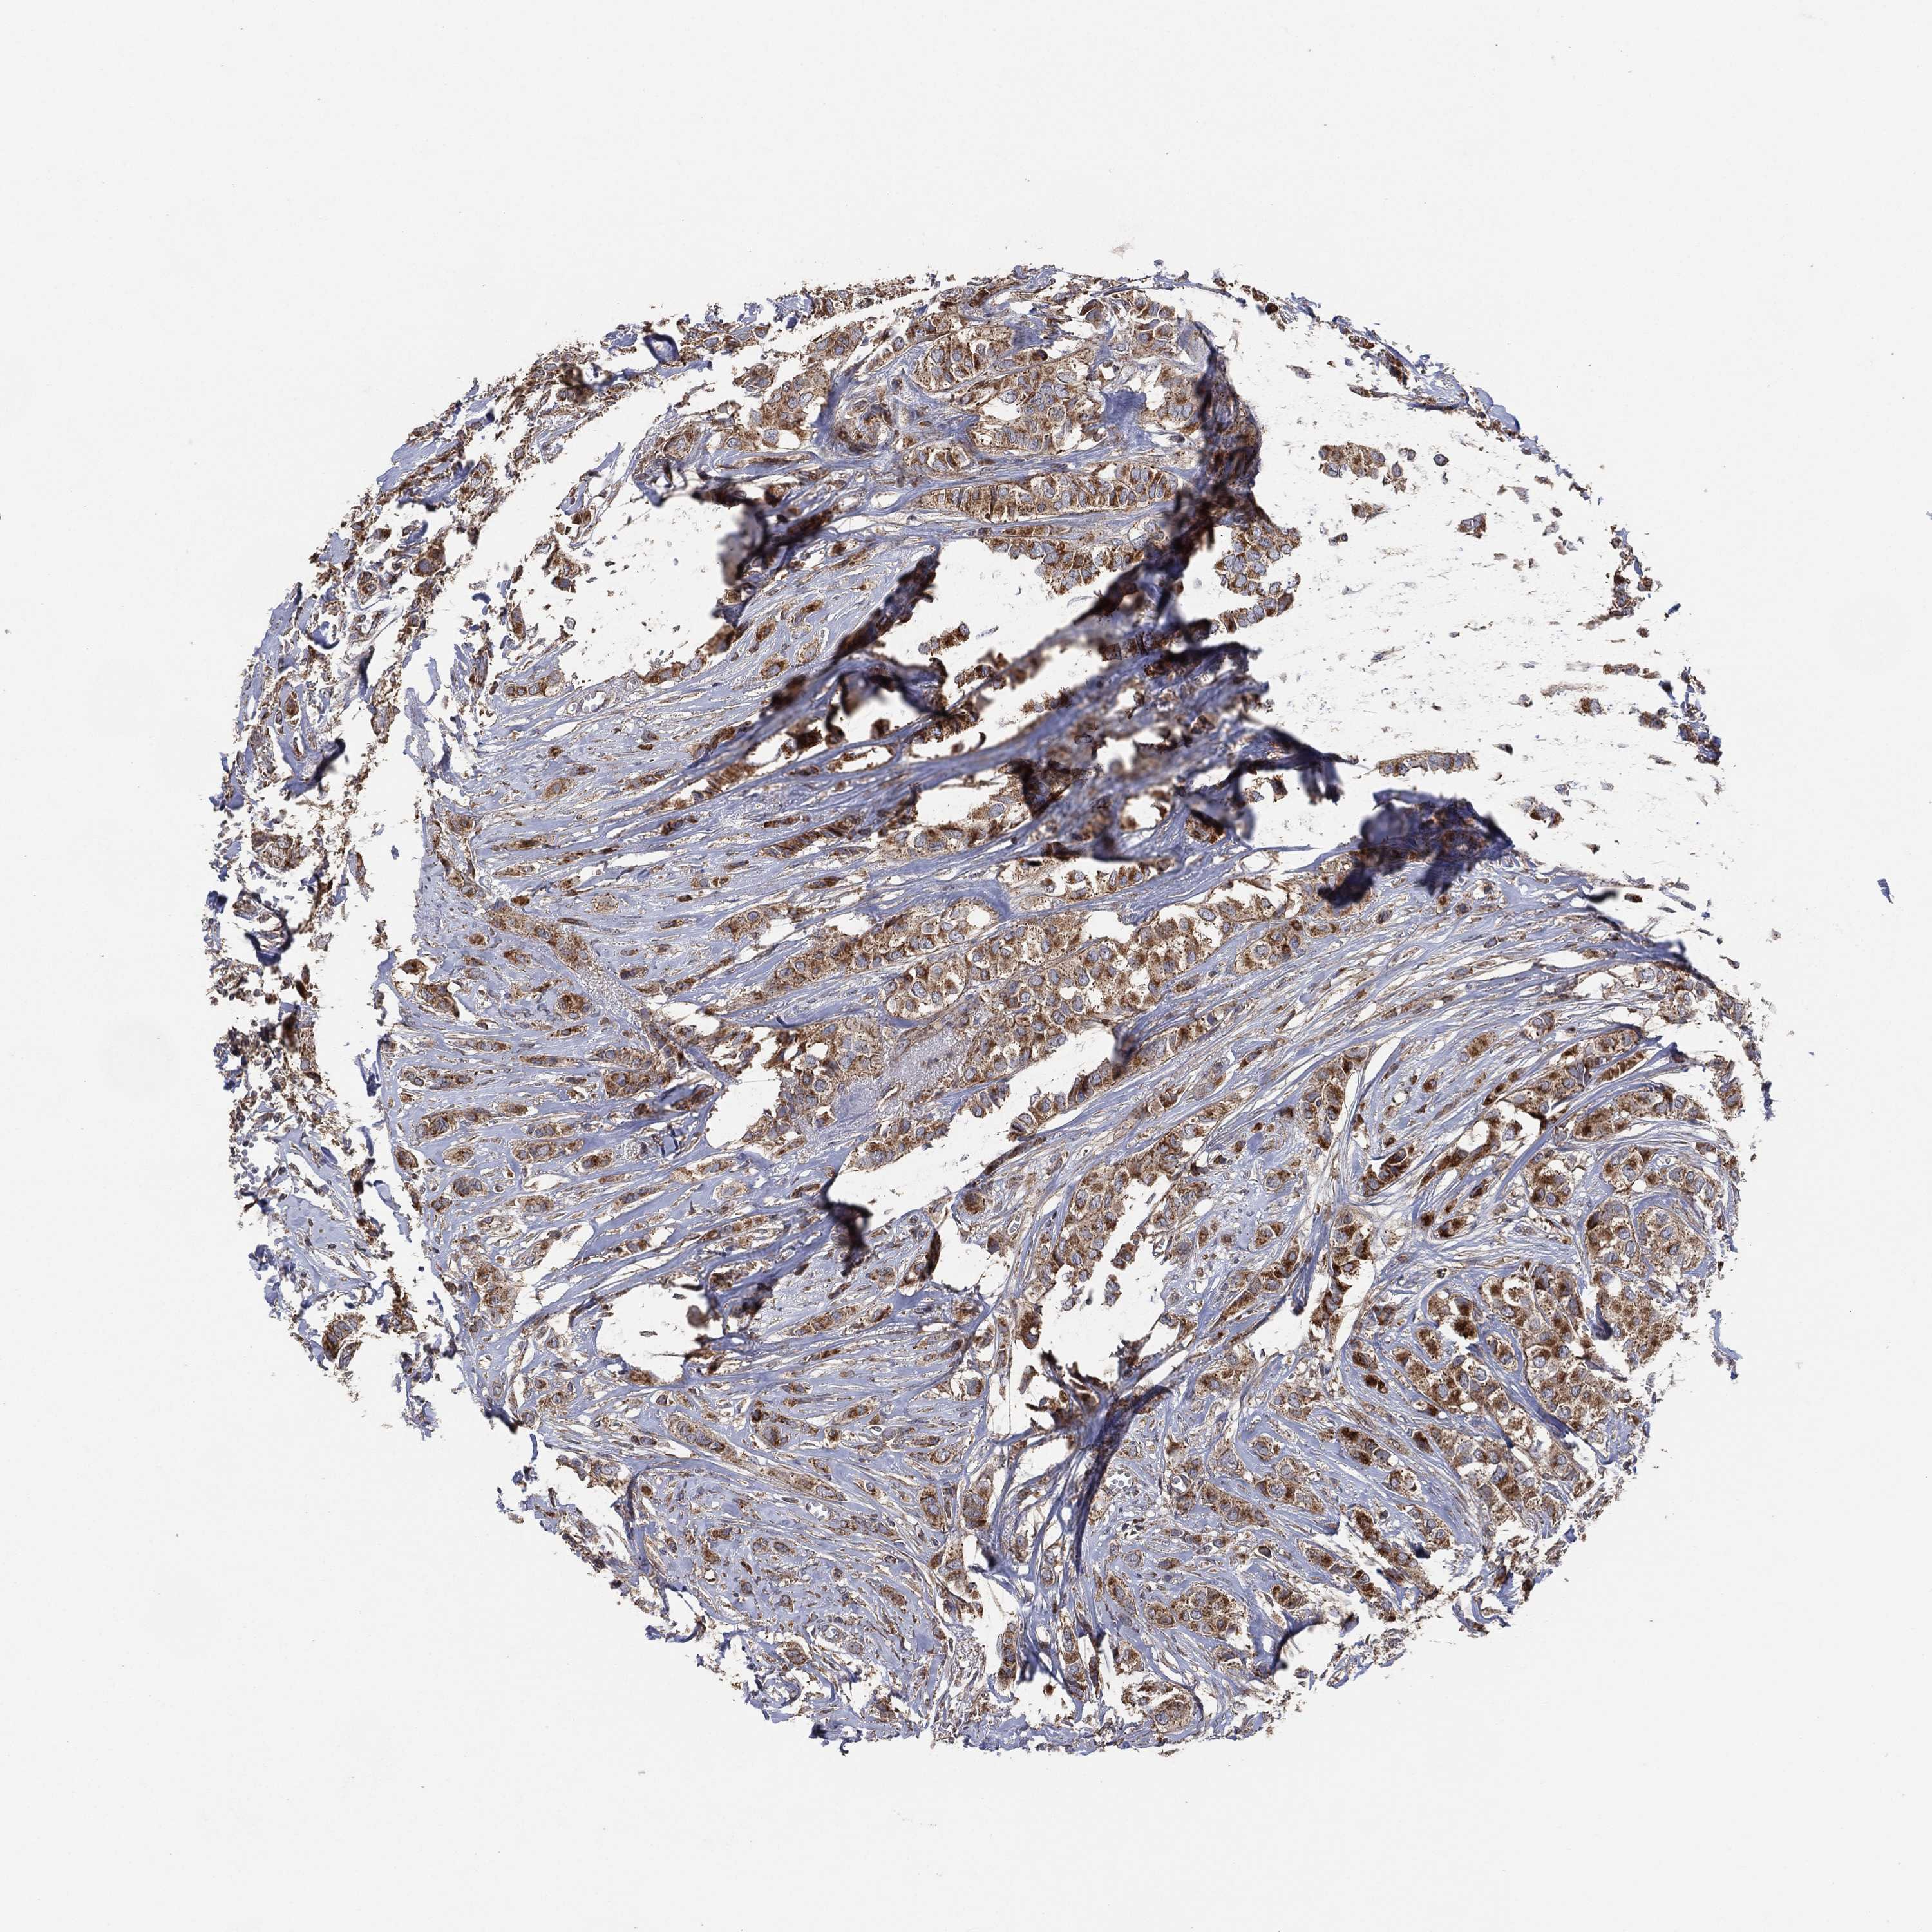

CANCER BREAST CANCER Show tissue menu

BRCA TCGA BRCA VALIDATION PROTEIN EXPRESSION